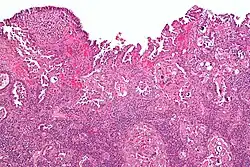

Histology H&E of uterine serous papillary carcinoma. H&E stain. |

Histopathologically, uterine serous carcinomas is typically characterized by (1) nipple-shaped structures (papillae) with fibrovascular cores (2) marked nuclear atypia (irregularities in the nuclear membrane, enlarged nuclear size), (3) psammoma bodies and (4) cilia. These are general findings in serous tumors which are also seen in such tumors in other anatomic locations.